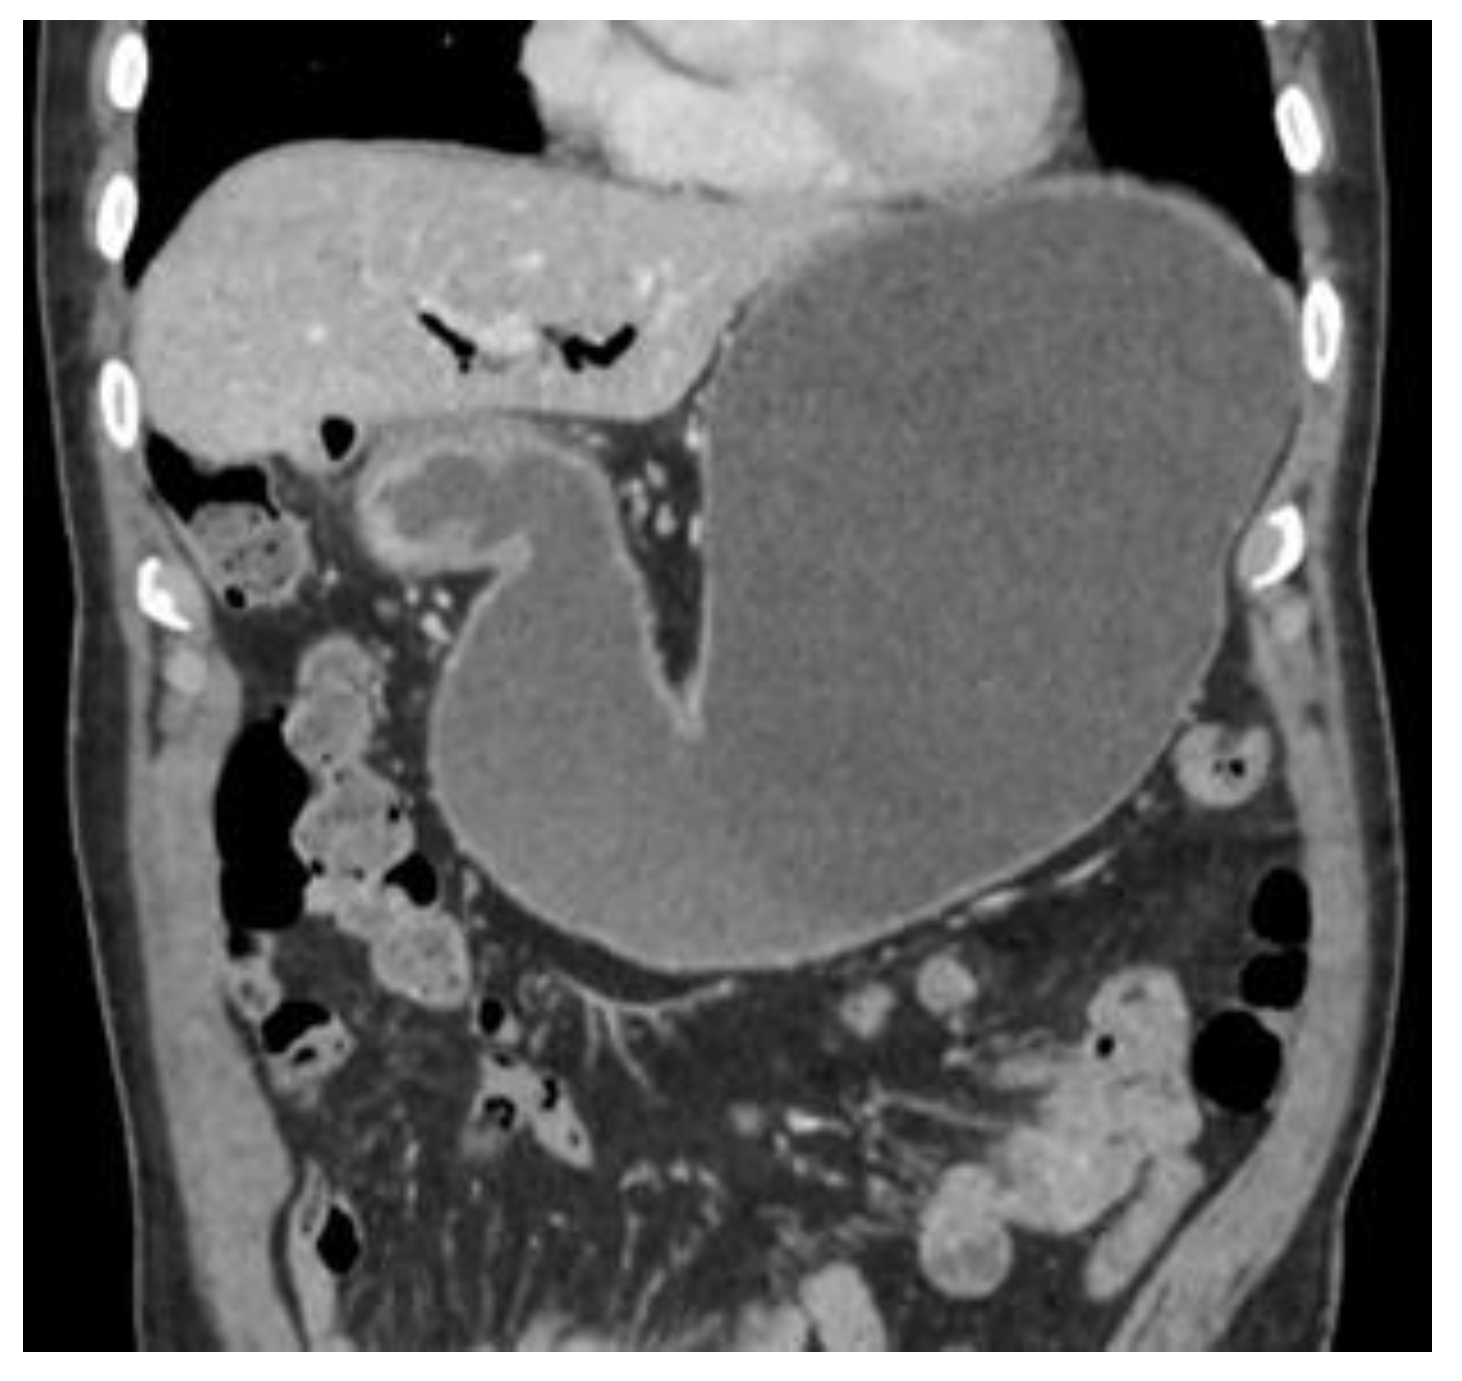

Figure 5 and Figure 6 Subsequent computed tomography with intravenous contrast material confirmed pneumobilia with direct visualization of a tract between the gallbladder and the duodenum and a 25 mm gallstone impacted in the duodenal bulb (long arrow) causing gastric distention so diagnosis of cholecystoduodenal fistula was made. Bouveret’s syndrome is characterized by gastric outlet obstruction (GOO) secondary to cholecystoduodenal fistula. [1,2] Fistula formation is favoured by the long history of cholelithiasis, the repeated episodes of acute cholecystitis, the large size of the gallstones (2–8 cm), the female gender and advanced age ( > 60 years ). Morbidity and mortality rates are high, estimated at 60% and 12%–30% respectively, due to the advanced age and the comorbidities of the patients. [3] Patients usually present with non-specific signs and symptoms of GOO, including nausea and vomiting in 87%, abdominal pain in 71%, hematemesis in 15%, weight loss in 14% and anorexia in 13%. [4] The radiologic features of gallstone ileus are the classical Rigler’s triad that consists of pneumobilia, dilated small bowel and an ectopic gallstone. [5] A plain abdominal X- ray is diagnostic in about 50% of cases and may demonstrate intestinal obstruction, pneumobilia, an ectopic gallstone, alteration in the position of the previously observed stone or two air fluid levels in the right upper quadrant secondary to air in the gall bladder. [6] US may show the gallstone sufficiently large to be apparent. The fistula may also be visualized if filled with fluid or air. Pneumobilia and a dilated stomach may also be seen with US. [7,8] CT is the best imaging technique used to search for Rigler’s triad that is specific to gallstone ileus and with it’s 93% sensitivity, 100% specificity, and 99% accuracy is needed for definitive diagnosis. [9] Up to 20% of the gallstones may be isoattenuating when MRI is indicated because it detects Rigler’s triad in nearly all cases where it was present. [10]

Figure 5. Computed tomography.